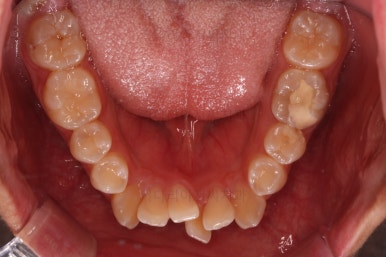

초진 시 입안의 모습입니다.

앞니가 많이 삐뚤고, 송곳니가 부각되어 덧니처럼 보이네요.

종료 시의 사진들을 전후 비교해 보겠습니다.

입매가 좋아졌고 입을 다무는 편안함도 좋아졌으며 치열이 가지런해졌으며 웃을 때 보이는 치열의 느낌도 좋고 교합도 잘 마무리 되었네요.